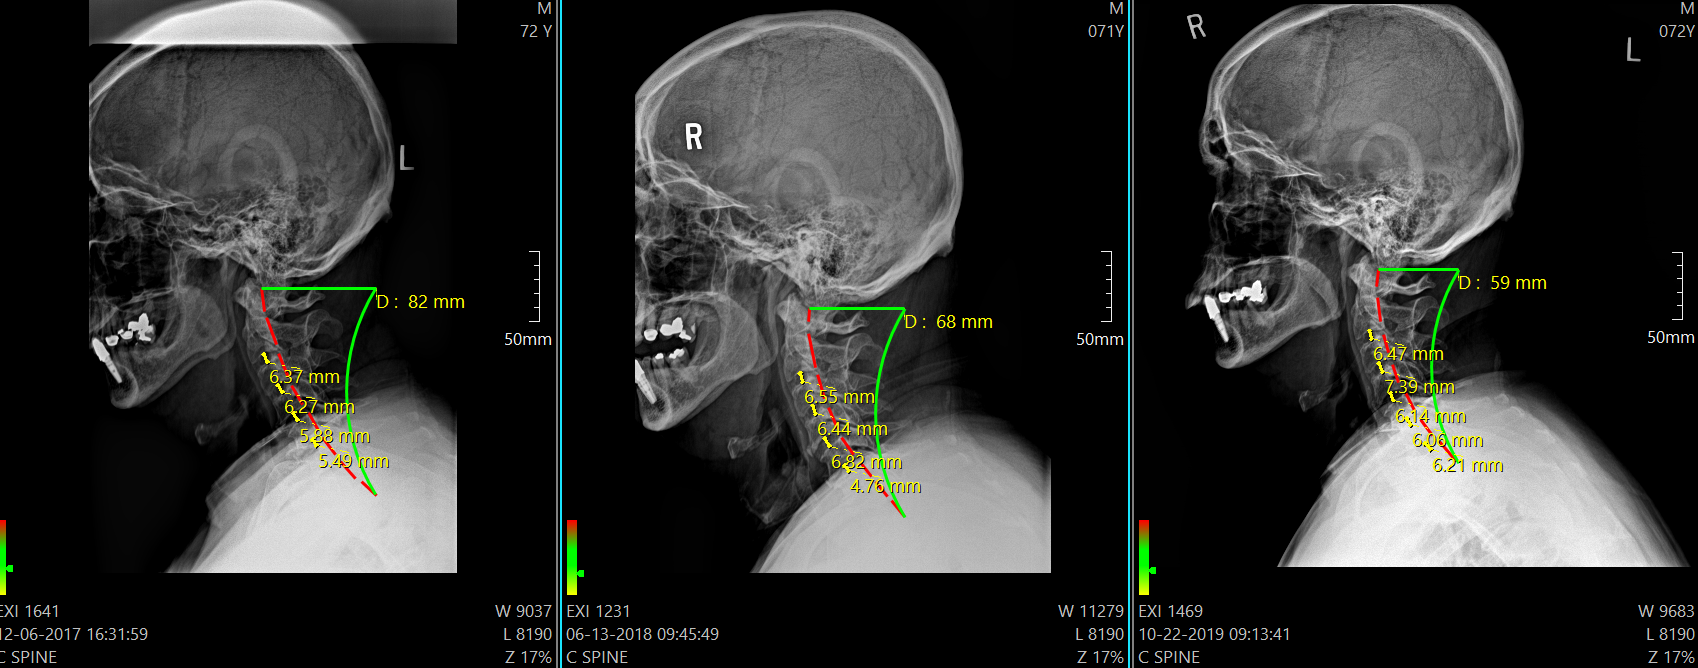

X-Rays (Objective)

This assessment is conducted using cutting-edge digital X-ray technology, ensuring precise imaging for accurate diagnosis and treatment planning. Typically performed on your first visit and during re-exam days, or as needed based on your unique care requirements, these X-rays are vital for understanding spinal health. The Blair cervical series includes specialized views such as Lateral, APOM (Anterior to Posterior Open Mouth), BP (Base Posterior), and Right & Left Protracto angles. These advanced imaging techniques provide detailed insights to guide personalized chiropractic care and ensure optimal results. Click here to learn more about xrays. https://www.spine-health.com/treatment/chiropractic/chiropractic-health-care-and-x-rays